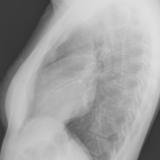

Case 1 Lat